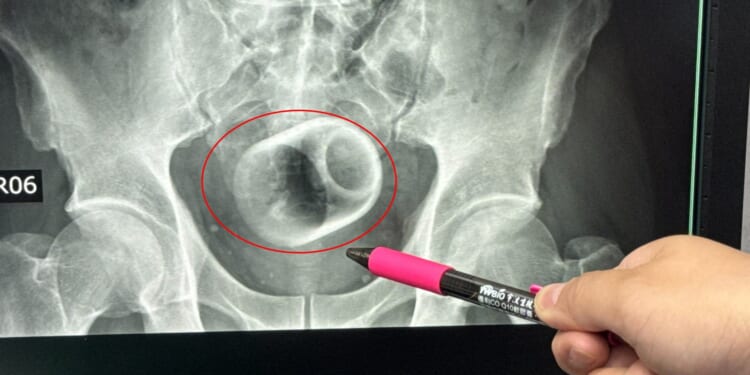

An X-ray revealed there was a ceramic cup inside him.

Measuring around 6cm wide and 8cm tall, medics tried to remove the piece of crockery.